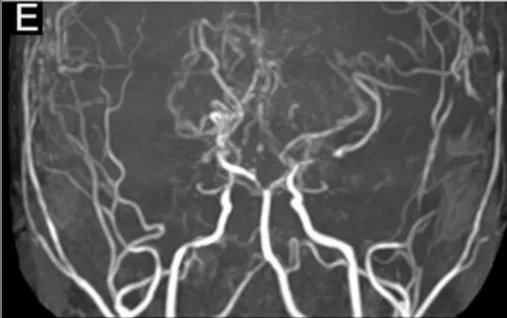

复查发现大脑后动脉(负责枕叶、顶叶供血,主管视觉和体感功能)狭窄加剧——首次手术虽解决前循环供血问题,但烟雾病作为进展性疾病,后循环血管持续狭窄,原有搭桥血管已无法满足供血需求,导致大脑再次缺血。

2年后MRA与DSA显示进行性大脑后动脉狭窄(图E)。